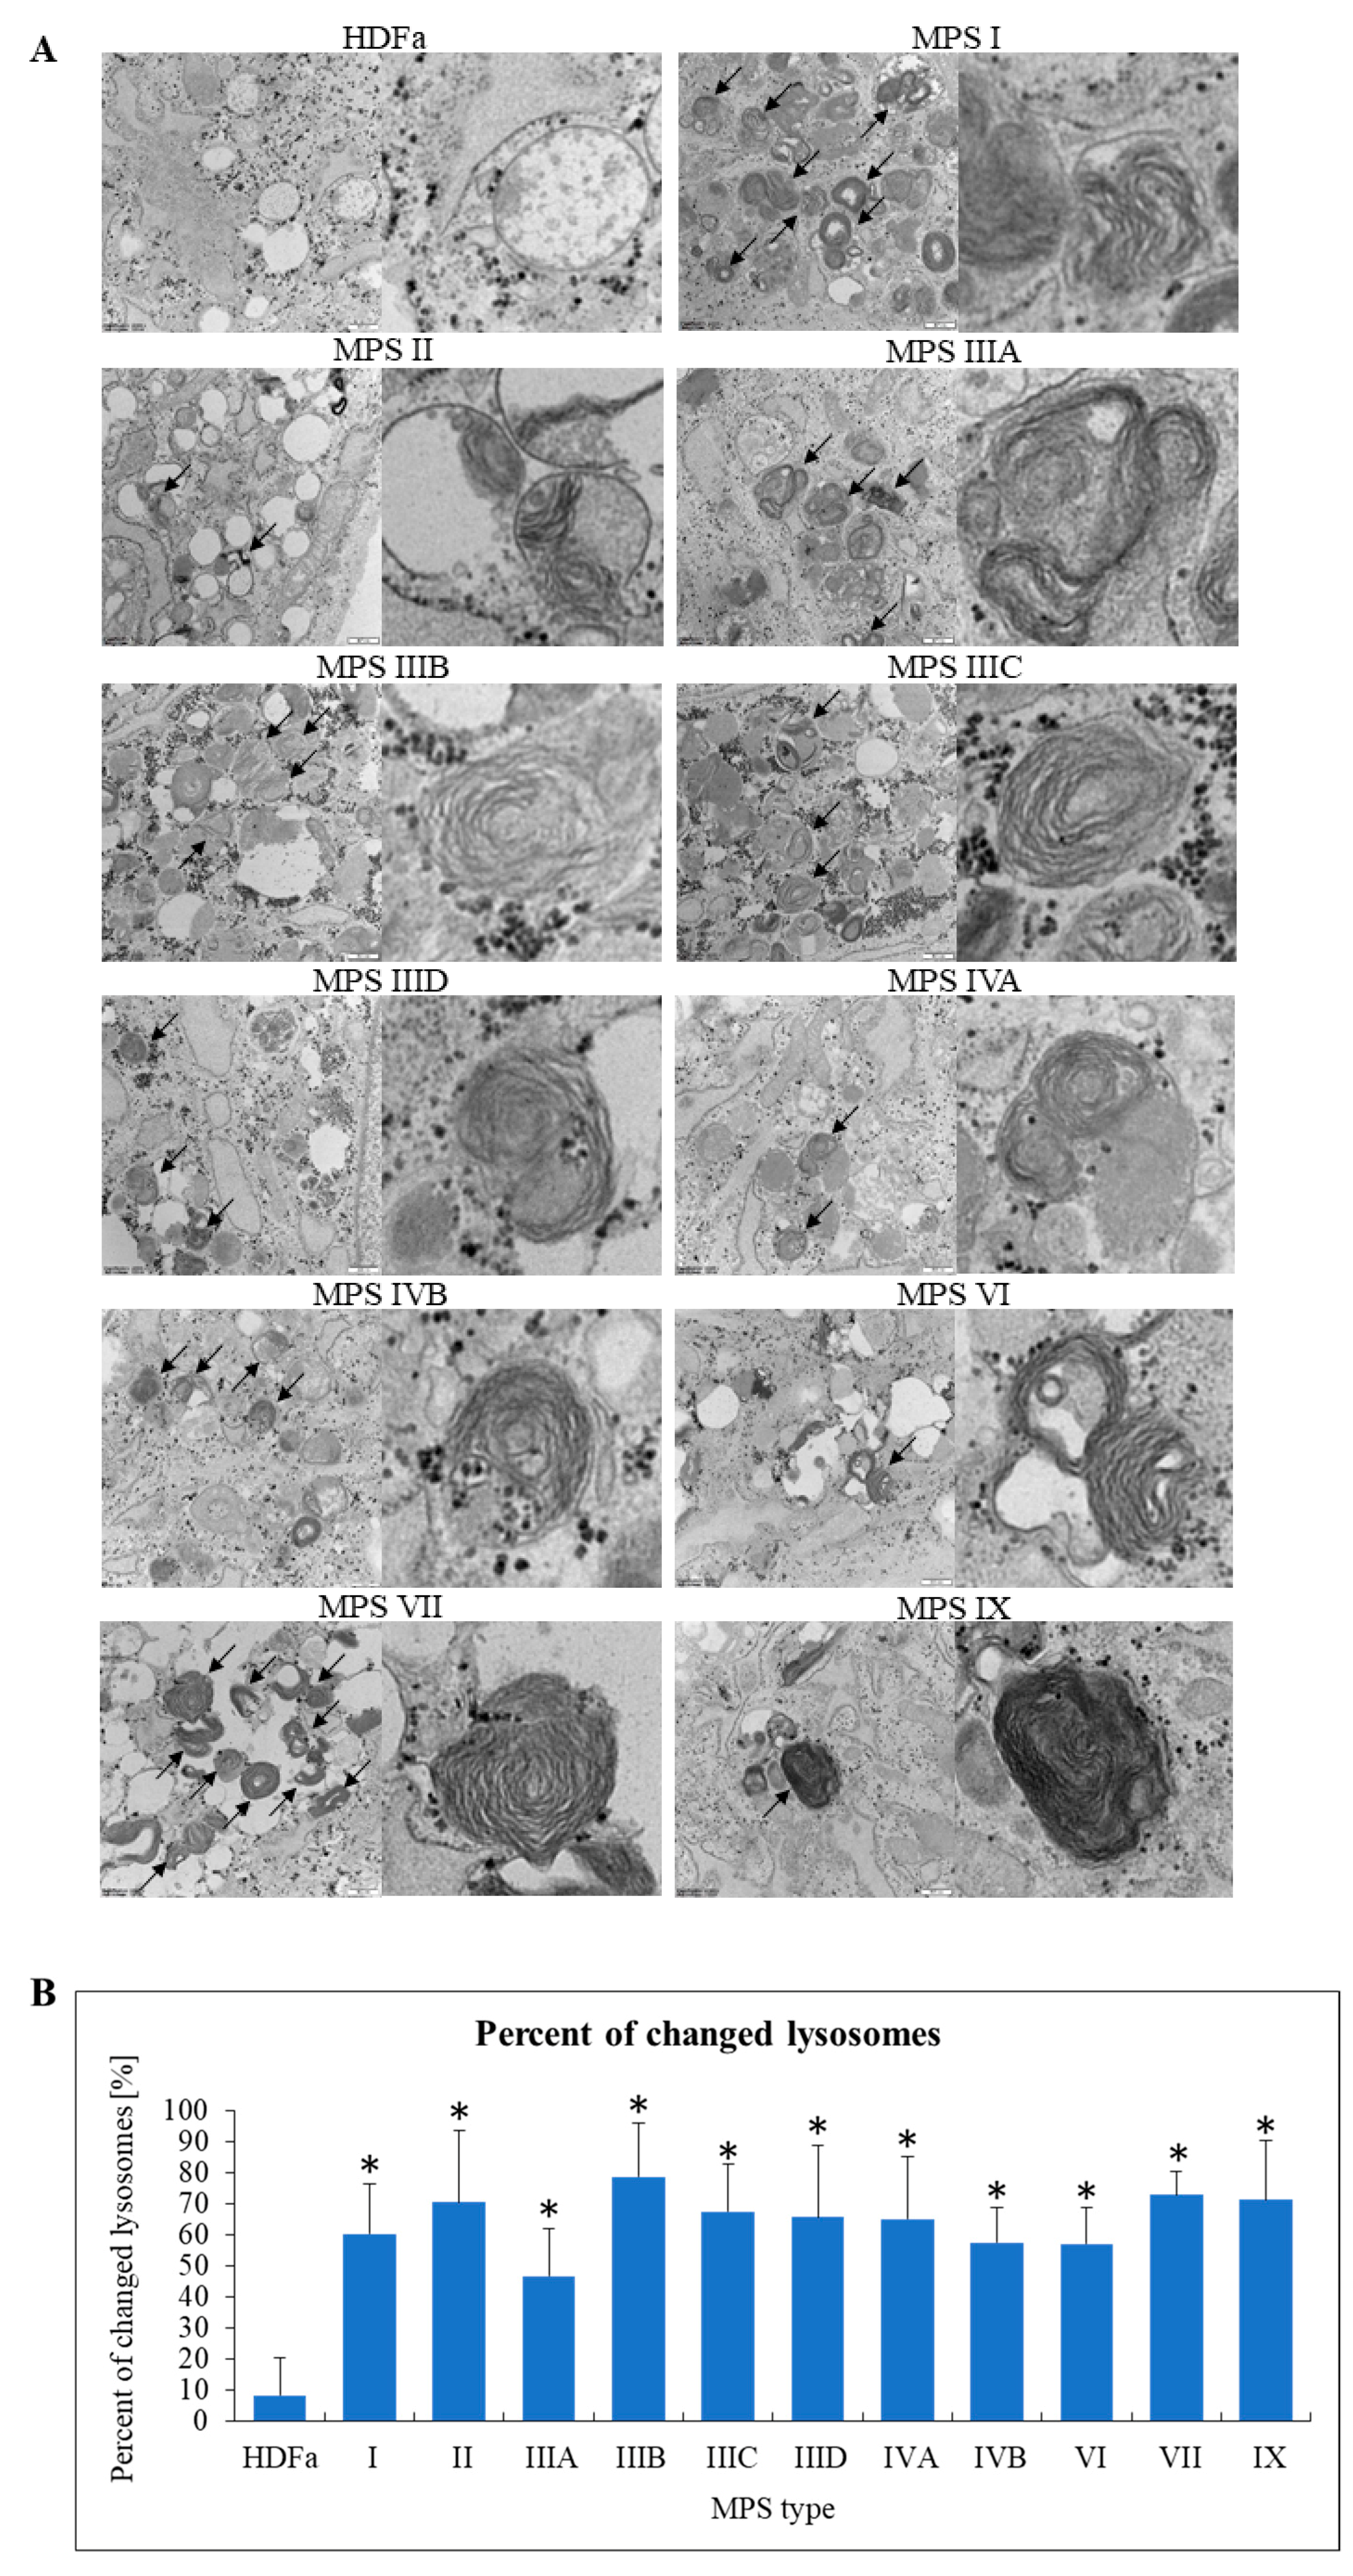

Since MPS belong to lysosomal storage diseases (LDS), we started our analyses from assessment of changes in these organelles. In fact, lysosomal changes in various MPS types have been widely described previously [4]. Therefore, assessment of lysosomes was, on one hand, a test for reliability of our experimental system, but on the other hand, our analyses allowed to perform simultaneous analyses of lysosomal changes in all MPS types/subtypes. Characteristic inclusions in lysosomes were observed, along with specific structures described previously (see [4] for details) as ‘onion skin’ and ‘zebra bodies’ (Figure 5A). These results confirmed that under experimental conditions used in our study, we were able to observe lysosomal changes described previously as characteristic for MPS. Moreover, we quantified our result by determining fractions (percentages) of changed lysosomes in all tested cell lines. In control cells, only a small percent of lysosomes revealed abnormalities in morphology, while in each MPS type/subtype the fraction of changes lysosomes was 45% (in MSP IIIA) or higher (Figure 5B).

Figure 5. Morphology of lysosomes in MPS fibroblasts in comparison to control cells (HDFa cell line). Representative electron micrographs are presented in (A) (size bars represent 500 nm; arrows indicate changes in these structures). Quantification of changes in lysosomes is presented in (B). Mean values ± SD are presented, with asterisks representing statistically significant (p < 0.05) differences relative to the HDFa control.